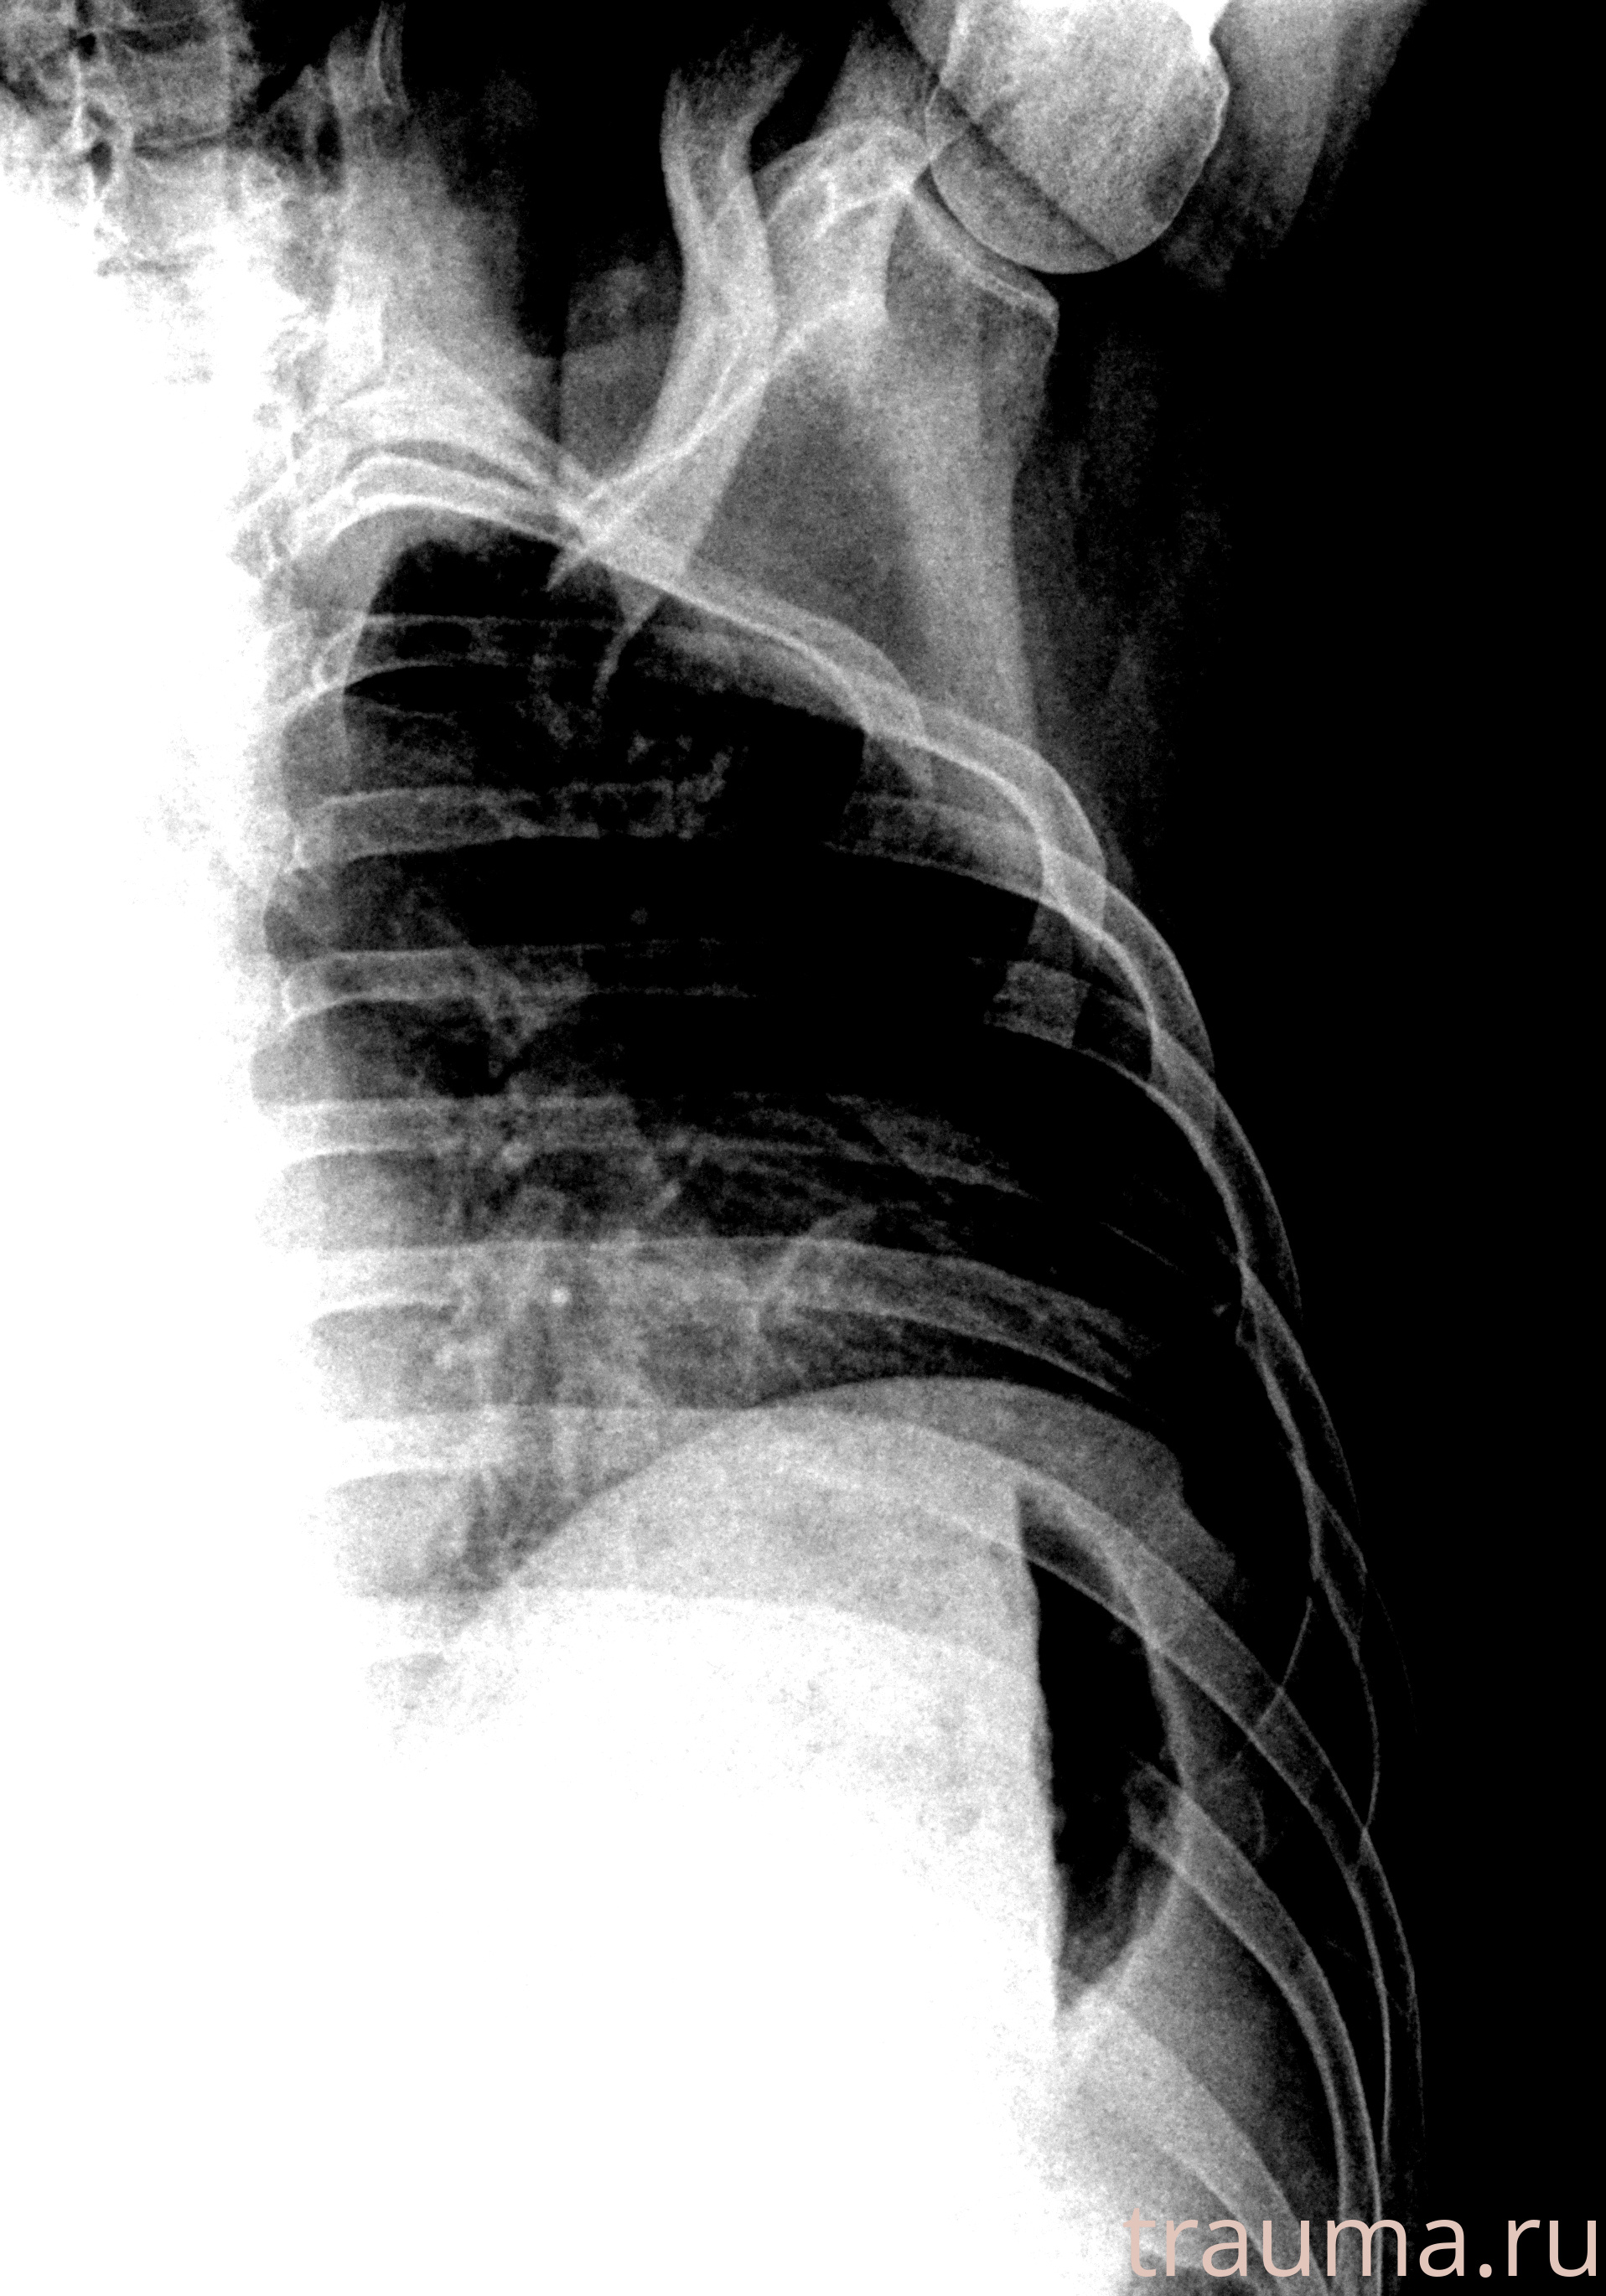

Рентгенограммы

Рентген на дому: по вашему адресу приезжает врач-рентгенолог, травматолог-ортопед с мобильным рентгеновским аппаратом, проводит диагностику травмы или заболевания, делает необходимые рентгенограммы, дает рекомендации по дальнейшему лечению. Получить качественные снимки в домашних условиях возможно благодаря уникальной методике, разработанной МосРентген Центром для института  Склифосовского

при переломе шейки бедра и пневмонии от компании МосРентген Центр - партнера Института имени Склифосовского